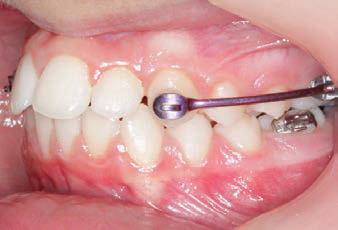

The SAGITTAL FIRST™ Philosophy is a time-tested approach that standardises, simplifies, and shortens Class II and Class III treatment times. It employs the Carriere Motion 3D Appliance to treat the AP dimension at the beginning of treatment before placing brackets or aligners. By resolving the most difficult part of treatment first, you can achieve a Class I platform in 3 to 6 months, shortening total treatment time by a minimum of 6 months1. You know how excited patients and parents become when you mention shorter treatment times.

INITIAL - 4/4/18

PROGRESS 1 - 26/9/18 - Class I platform accomplished in 5.75 months with Motion 3D COLOR Appliance

PROGRESS 2 - 26/9/18 - Placement of the SLX 3D Clear Brackets

with M-ONE .015 Cu Nitanium 27°